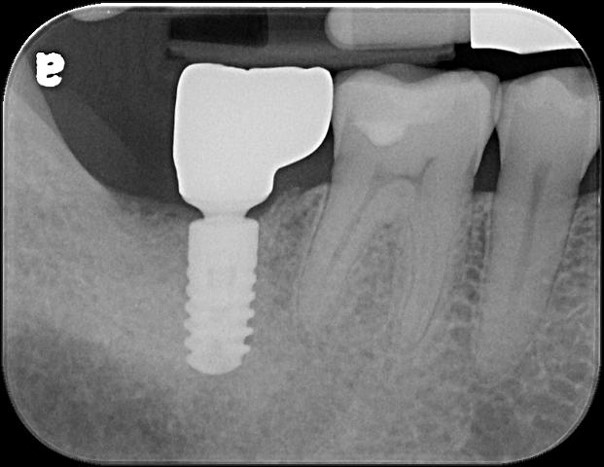

蛀牙未到牙髓

冠塊體體製備